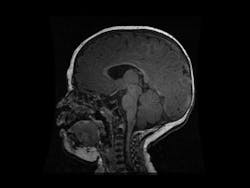

For instance, a team of American researchers used AI to aid detection of autism in babies as young as six months1. This is crucial because the first two years of life see the most neural plasticity when the abnormalities associated with autism haven’t yet fully settled in. This means that earlier intervention is better, especially when many autistic babies are diagnosed at 24 months. While previous algorithms exist for detecting autism’s development using behavioral data, they have not been effective enough to be clinically useful1. This team of researchers sought to improve on these attempts by employing deep learning. Their algorithm successfully predicted diagnoses of autism using MRI data from babies between six and 12 months old. Their system processed images of the babies’ cortical surface area, which grows too rapidly in developing autism. This smarter algorithm predicted autism so well that clinicians may now want to adopt it.